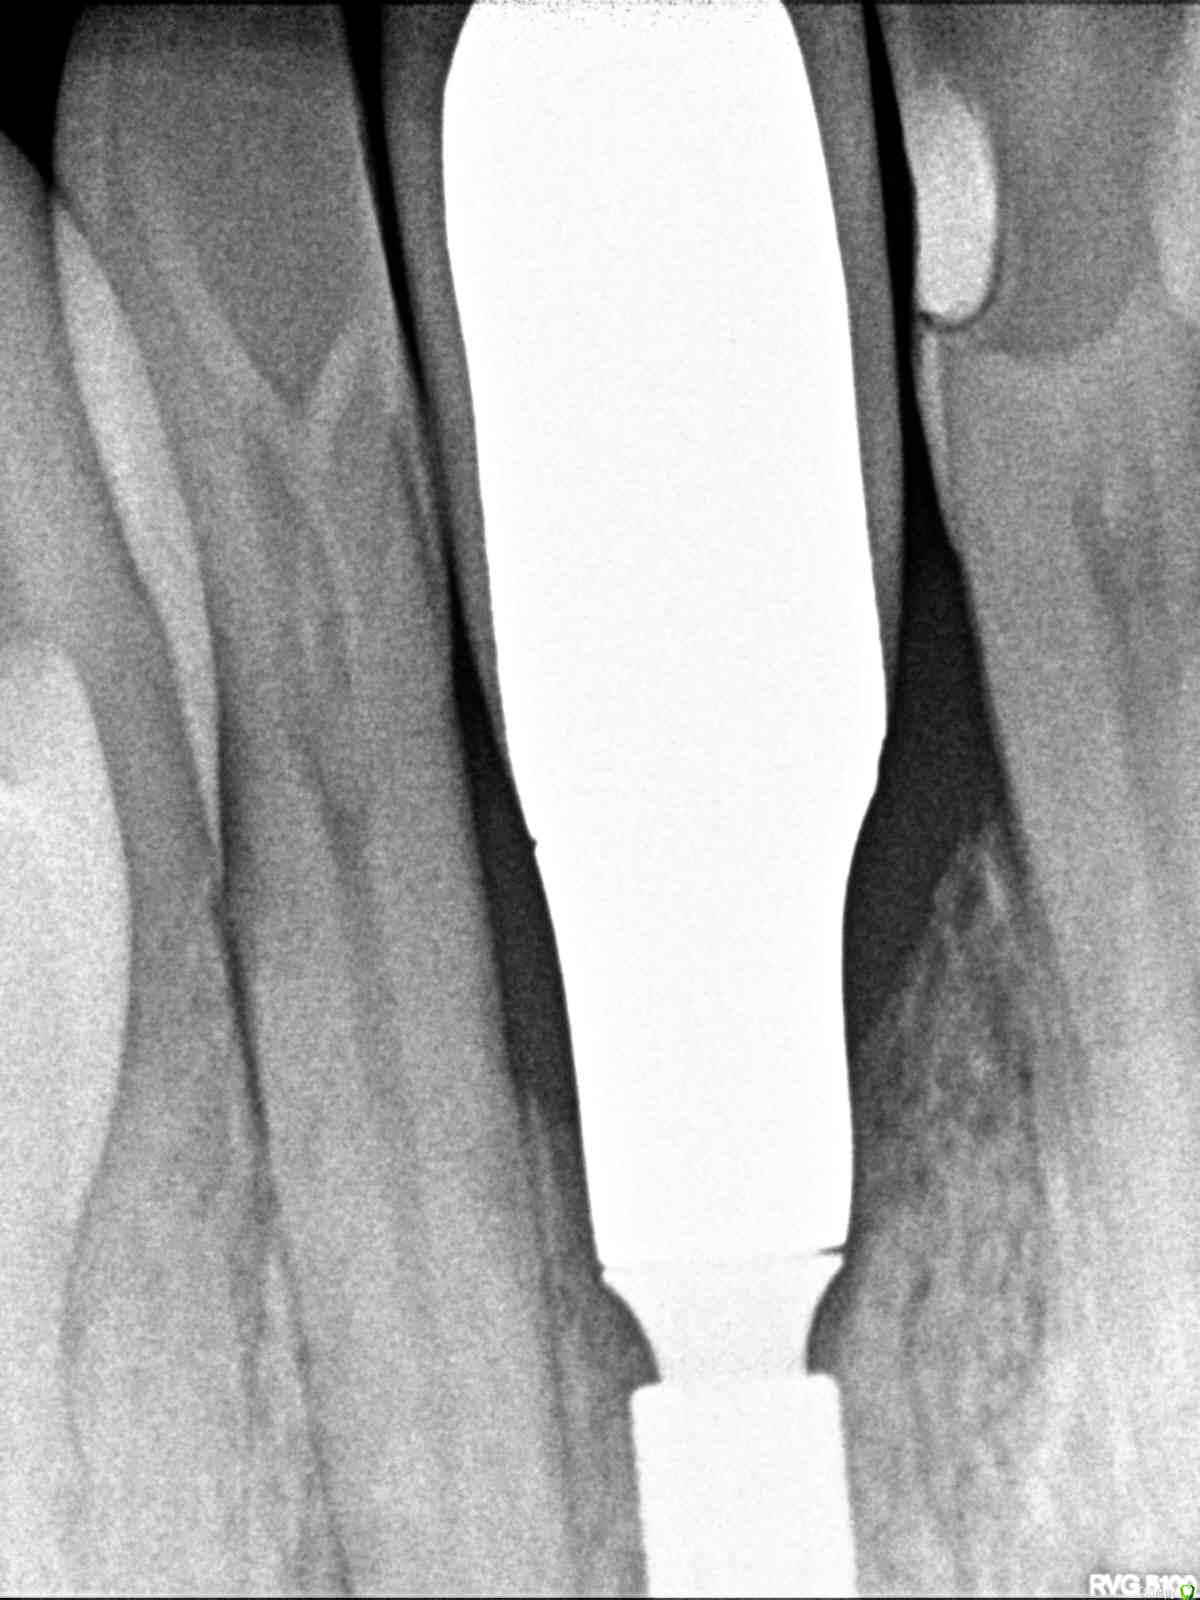

Irouil Опубликовано 6 декабря, 2018 Поделиться Опубликовано 6 декабря, 2018 С другой стороны, щель между имплантатом и абатментом находится глубже в кости и в большой степени спровоцирует резорбцию. Вы на сколько заглубляете обычно?При переключении платформы пространства между хирургической и ортопедической достаточно, чтобы мягкотканное прикрепление легло на все соединение имплантат/супраструктура, герметизируя щель. Естественно, чем меньше тревожить в дальнейшем это соединение - тем меньше будет резорбция вообще. Ну и ортопедия. Ортопед должен понимать куда и почему, отдавать себе отчёт где хирургическая платформа, где должна быть ортопедическая и с какого уровня он может начинать работать. А то получается вот так в итоге Ссылка на комментарий